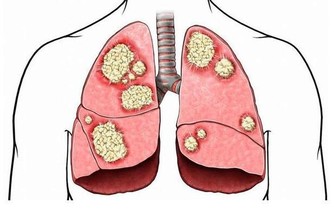

壹週刊報導,台大醫院新竹分院皮膚科醫師邱顯鎰表示,乾癬是一種自體免疫疾病,

患者如果感冒、壓力大,或生活上遇重大事件發生時,就容易誘發乾癬發作。

根據統計,台灣乾癬患者並不少,大約1/3經過一次治療就好轉許多,

但剩下2/3症狀可能會愈來愈糟(約3成患者會惡化成乾癬性關節炎),

且必須一直持續治療,嚴重的話甚至會無法行走。